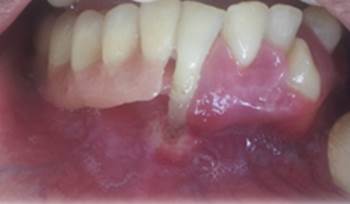

En el examen físico extraoral se observó frente prominente, tercio medio facial disminuido, hombros plegados con tórax excavado, dedos en forma de palillo de tambor, piel delgada y reseca, hiperfuncionalidad de la articulación del hombro. Mientras tanto, en la revisión estomatológica se observaron labios delgados, semi mucosas labiales con múltiples escamas y surcos labiales marcados, zona eritematosa intensa en mucosa palatina de paladar duro, con aspecto granular, halo blanquecino que delimita paladar duro del blando (Imagen 1); encía marginal y adherida con fuerte inflamación, eritematosa, engrosada, lisa y brillante de forma generalizada (Imagen 2); recesión gingival a nivel de encía marginal palatina y vestibular de órganos dentarios superiores. En la prueba de movilidad dental se evidencia movilidad horizontal y axial generalizada grado II y III para los órganos dentarios inferiores y II para los superiores.

A nivel de los rebordes alveolares superior e inferior se observó y palpó irregularidad acentuada en zona anterior, asociada a múltiples exodoncias realizadas en esta región de los maxilares.